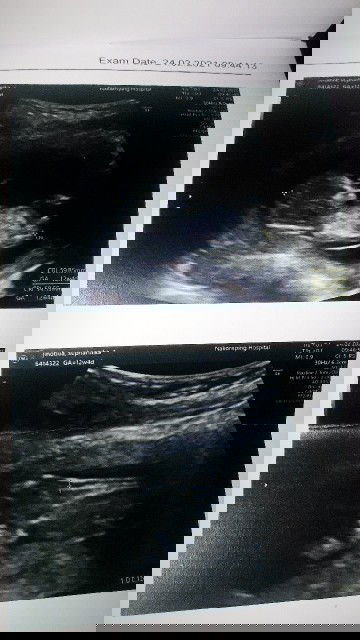

อัลตร้าซาวด์ครั้งแรกจากที่รอเห็นมานาน ได้ฟังเสียงหัวใจครั้งแรกตื่นเต้นมาก 💓💓 #12_weeksand4_days